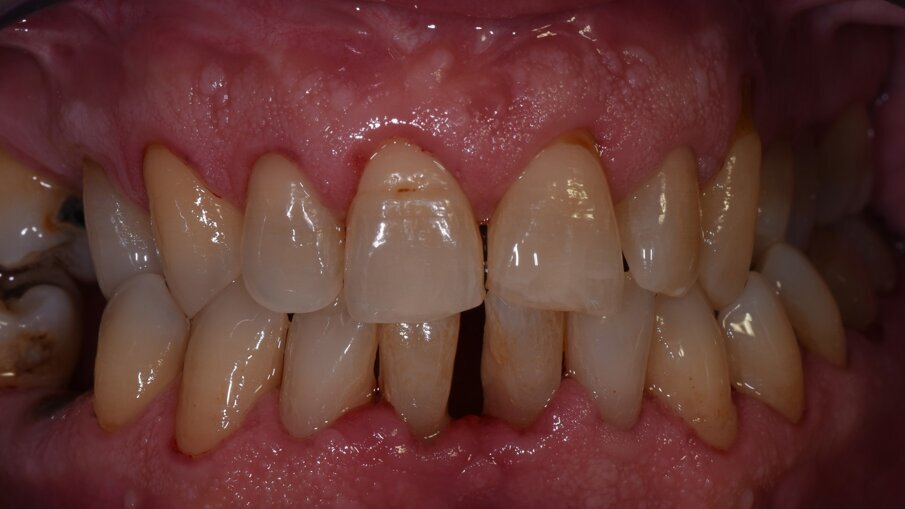

Passiamo poi al debridment parodontale con ablatore pizoelettrico Comby Touch Mectron e successivamente facciamo visualizzare al paziente le grosse concrezioni di tartaro presenti nell’area linguale e facciamo osservare la considerevole ampiezza biologica dello spazio interprossimale dato dalla recessione della papilla interdentale (Figg. 5a-5c). Mostriamo quindi la necessità di utilizzare lo scovolino professionale GUM TRAV-LER (Fig. 5d) con ampiezze diverse per essere efficaci nel controllo del biofilm batterico a livello interincisivo. Al follow-up il paziente presenta indici clinici sensibilmente migliorati e riferisce di sentirsi soddisfatto perché dotato finalmente di strumenti in grado di agevolarlo nel difficile compito di tenere sotto controllo l’efficacia della sua igiene orale domiciliare (Figg. 6a-6c).